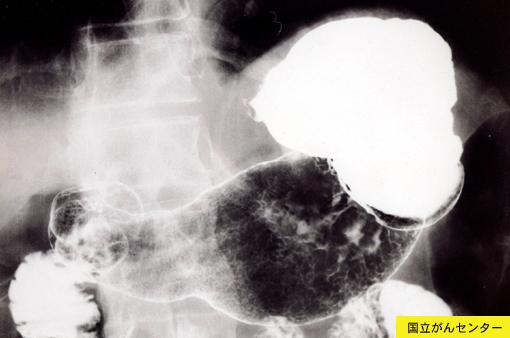

Tumor Linfático Maligno de Estómago, que demuestra la similitud al cáncer avanzado del estómago

Tumor Maligno del Sistema Linfático/Linfoma Maligno

estómago(región)/mas de dos

Rayos X

40 -

ss(a1)